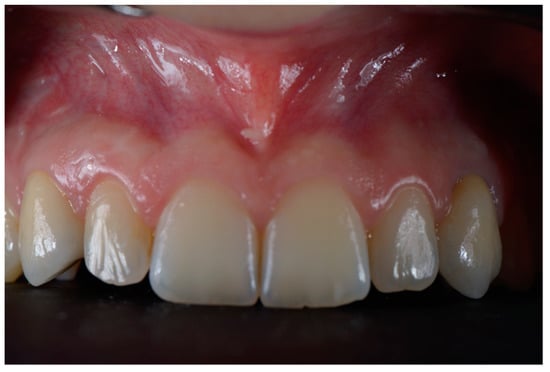

:1. Introduction

2. Materials and Methods

2.3. Surgical and Prosthetic Workflow

2.4. Outcome

3. Results